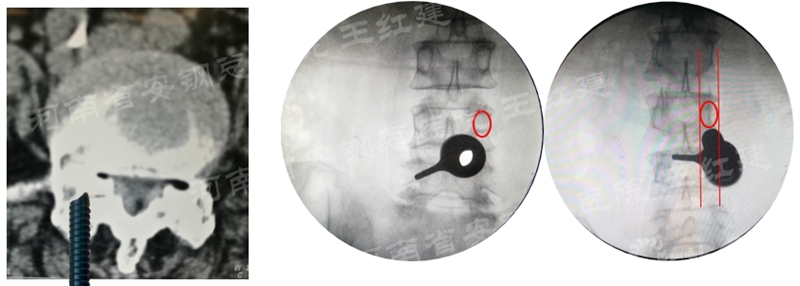

应用通道技术进行植入融合时,首先要更换工作套管,通过枪钳、抓钳的应用处理椎间盘,接着进行自体骨或同种异体骨及cage植入,并通过C臂透视确定试模型号放置融合器,最终完成植骨融合。

确定融合器位置

四、经皮螺钉技术固定

在固定的步骤可以先期进行经皮螺钉置入,再进行融合器的置入,进而实现充分固定。

椎弓根植入加压固定

单边椎弓根植入加压固定

双侧椎弓根植入加压固定

手术步骤:先期经皮螺钉置入、再进行融合器的置入